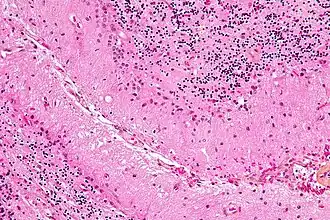

Bergmann-gliacel (ook bekend als Bergman-gliacel, radiale gliacellen, Golgi-epitheelcellen of radiale astrocyten) zijn unipolaire astrocyten die zijn afgeleid van radiale gliacellen en nauw verbonden zijn met purkinjecellen in de schors van de kleine hersenen.[22] Omdat Bergmann-gliacellen in de kleine hersenen lijken te blijven en veel van de rollen vervullen die kenmerkend zijn voor astrocyten, worden ze ook wel "gespecialiseerde astrocyten genoemd."[12] Bergmann gliacellen hebben meerdere radiale uitlopers die zich uitstrekken over de moleculaire laag van de kleine hersenen en eindigen aan het oppervlak van het zachte hersenvlies als een bolvormige eindvoet.[23] Bergmann gliacellen helpen bij de migratie van korrelcellen, door de kleine neuronen van de externe korrelcellaag naar de interne korrelcellaag te leiden langs hun uitgebreide radiale uitsteeksels.[24][25] Naast hun rol in de vroege ontwikkeling van de kleine hersenen zijn Bergmann gliacellen ook nodig voor synaptische pruning.[26] Na de dood van de purkinjecel als gevolg van een verwonding aan het centrale zenuwstelsel, ondergaan Bergmann gliacellen uitgebreide proliferatieve veranderingen om verloren of beschadigd weefsel te vervangen in een proces dat bekendstaat als gliose.[27][28]